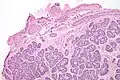

| Micrograph of a Sertoli cell nodule. H&E stain. | |

Sertoli cell nodules are unencapsulated nodules that consist of:[2][3][4]

- cells arranged in well-formed tubules (that vaguely resemble immature Sertoli cells), with

- bland hyperchromatic oval/round nuclei that are stratified, and

- may contain eosinophilic (hyaline) blob in lumen (centre).